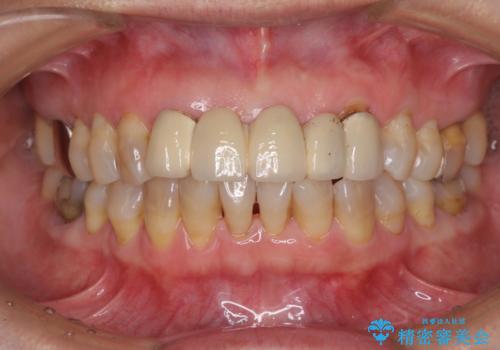

- アンバランスな色や形、歯肉ラインの黒い縁が目立ってしまったブリッジの作り直しを希望して来院された患者様です。

自然な仕上がりとするため、金属を使用しないオールセラミックブリッジにより補綴治療を行うこととしました。

装着されていたブリッジは、支台となっている歯と欠損している歯で色が大きく異なっていましたが、オールセラミックとしたことで、全体的に色調の整った仕上がりとなりました。

歯肉ラインがきれいに整い、患者様には大変満足していただきました。